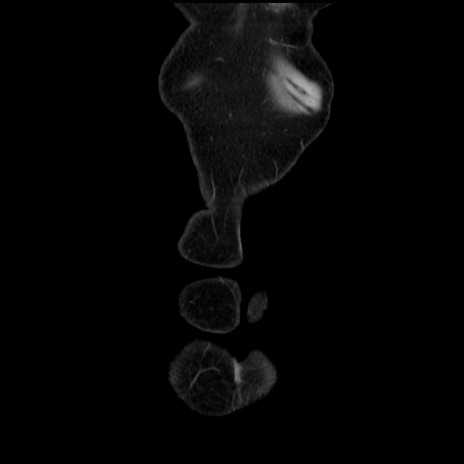

矢状断像